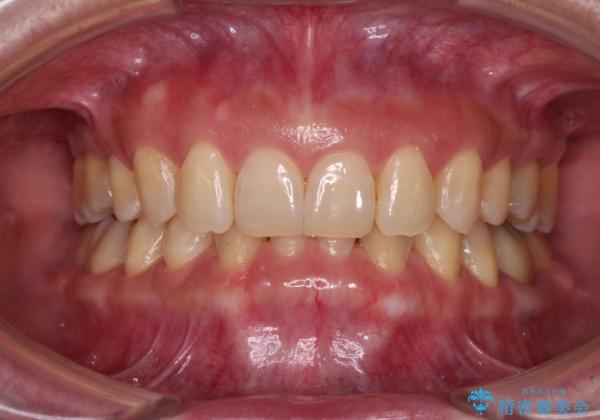

下顎2前歯の欠損 インビザラインによる抜歯矯正

- 下顎前歯欠損による歯列不正を気にして来院された患者様です。

下顎の歯列が小さく、下顎前歯が隠れてしまう過蓋咬合(ディープバイト)であったため、

マウスピースでの抜歯矯正特有の抜歯スペースに向かって奥歯が傾斜する動きが顕著に表れ、ディープバイトは改善されませんでした。

前歯のみが強く接触し、奥歯で咬めない期間も続いたため、ワイヤー装置などを補助的に使用し、何とか終了させることができました。